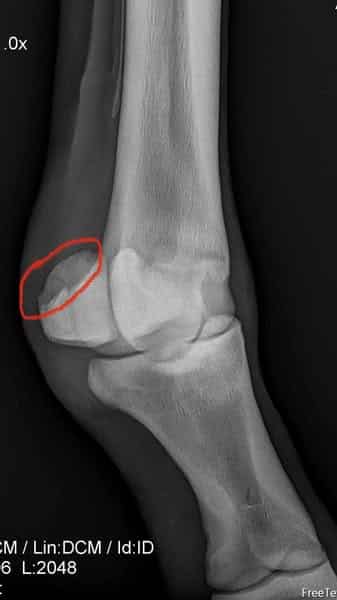

Severe cases of sesamoiditis may also show calcification of the soft tissue structures around the area, or an avulsion fracture (small piece) coming off the sesamoid. (Hagyard Facebook photo)

Diagnosis comes through radiographs; in Canada, all Thoroughbred yearlings at the Canadian sale are x-rayed ahead of time, and veterinarians will look at the x-rays and diagnose sesamoiditis at that point.